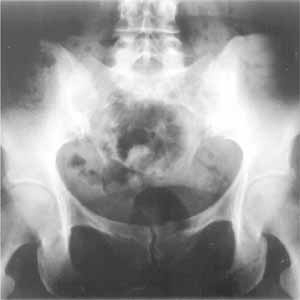

Abbildung 4

Unterschiedliche Iliosakralgelenksstrukturen wie auch eine unterschiedliche Gewebsdichte in dem an dieses unmittelbar anschließende Knochen- und elastische Bindegewebe bei der diesbezüglichen Beurteilung einer a.-p.-Röntgenaufnahme des Beckens weisen auf Bewegungsasymmetrien beider Iliosakralgelenke im bezug zueinander hin. Das breite und gut konturiert konfigurierte Iliosakralgelenk mit weniger dichtem Umgebungsgewebe ist meist das ligamentär hypomobile [rechte Beckenhälfte/linke Bildhälfte], das mit den teilweise inkongruenteren Gelenkstrukturen und hellerem = dichterem umgebendem Gewebe ist als das ligamentär hypermobile anzusehen, welches durch nozizeptiven mehr oder weniger starken Dauerreiz das muskulär-funktionell „blockierte” ist (die gesamte Lage des Os coccygis stellt sich auf dieser Aufnahme, wie häufig, nicht entsprechend dar und ist somit nicht zur Beurteilung der Bänderspannung auswertbar [linke Beckenhälfte/linke Bildhälfte]).

Die Darstellung der Gesamtlage des Os coccygis auf einer solchen Aufnahme ist meist ungenügend und für oben angesprochene Aussagen zur Auswirkung der Bänderspannung auf das Steißbein wenig geeignet, da dessen distale Gewebsdichte an der Apex coccygii häufig gering ist und sich somit nur unklar, je nach Belichtung und Filterung bei der Aufnahme, darstellt (lediglich im Versuch haben sich uns hierzu spezielle Aufnahmetechniken bewährt, die in der Praxis jedoch für die Befunderhebung nicht nötig sind).